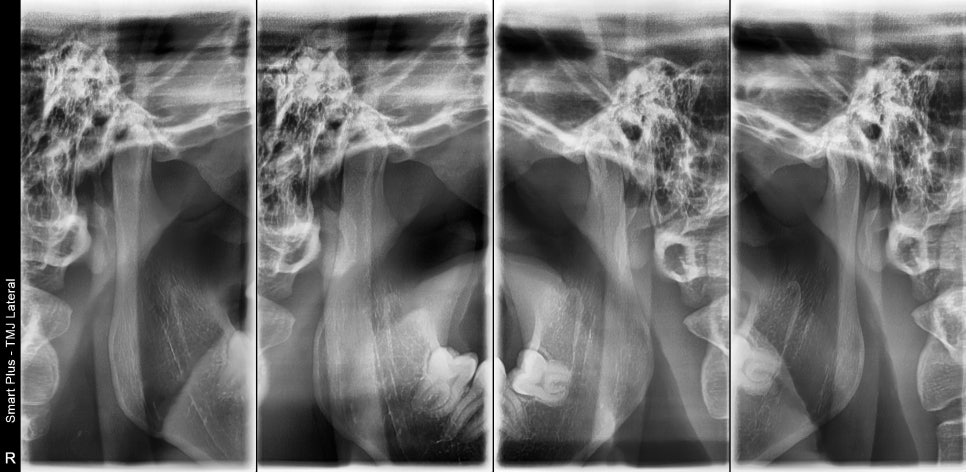

문진, 촉진을 통해 어느 부분이 문제 인지 확인하고, 턱관절이 문제인지 확인을 위해 턱관절 방사선 사진을 찍어봅니다.

위의 사진은 우리가 입을 다물고 벌릴 때, 턱관절의 위치를 확인 위해 찍는 사진입니다.

해당 사진에서 턱관절 쪽으로 이상이 없다고 확인을 하고 근육 쪽의 문제인지 촉진을 해봅니다.